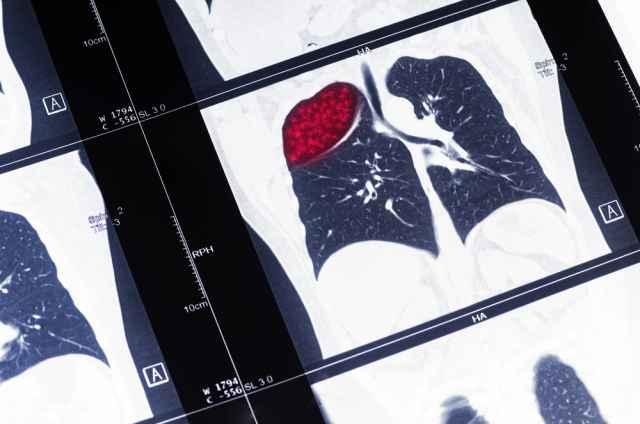

Keberadaan jaringan abnormal atau benjolan di paru-paru dapat dideteksi melalui pemeriksaan medis, seperti rontgen dada (X-ray) dan computed tomography scan (CT scan).

Jika hasil pemeriksaan menunjukkan adanya tumor, dokter kemungkinan akan melakukan bronkoskopi untuk menentukan apakah tumor bersifat ganas atau jinak.